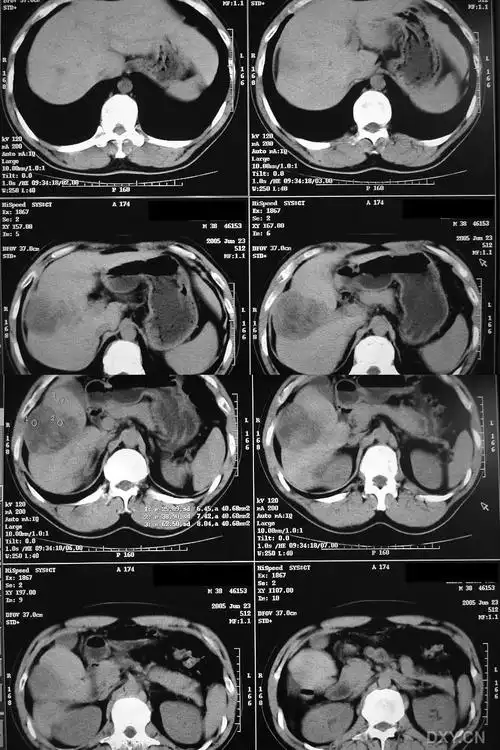

【请教】肝脏ct